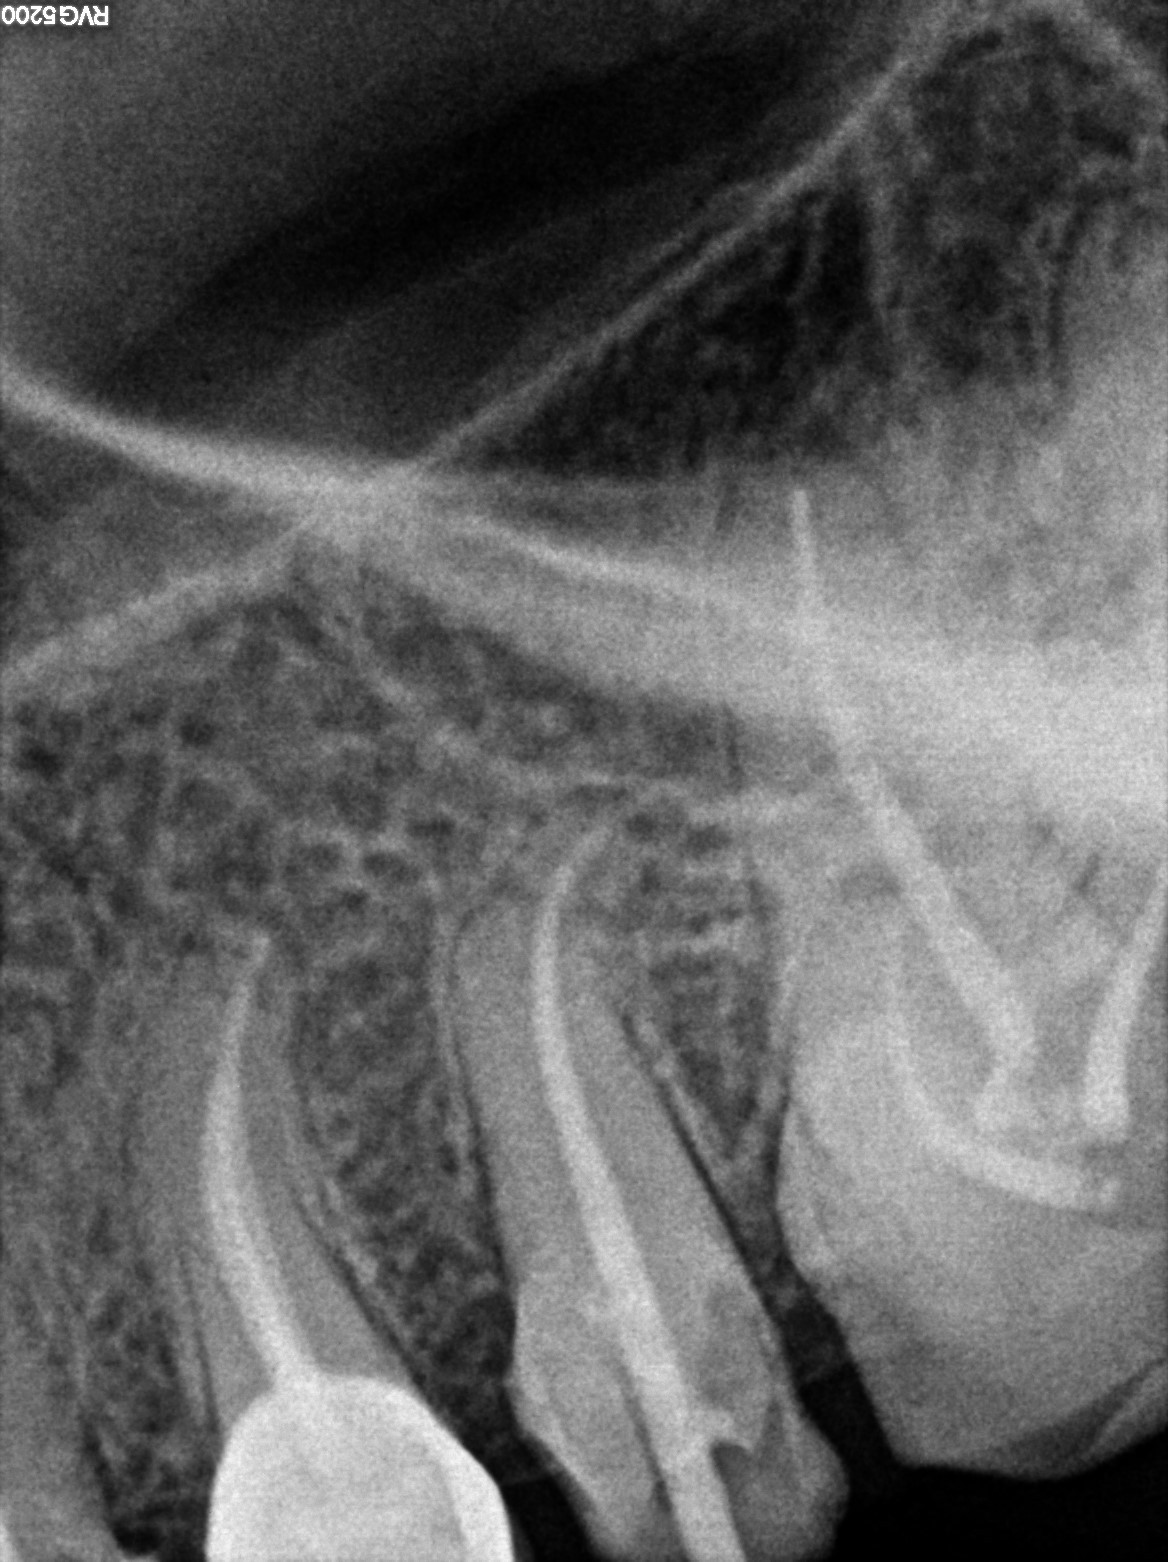

Dental Radiographs FHIR: DocumentReference · LOINC 24641-7

R38.jpg

24641-7